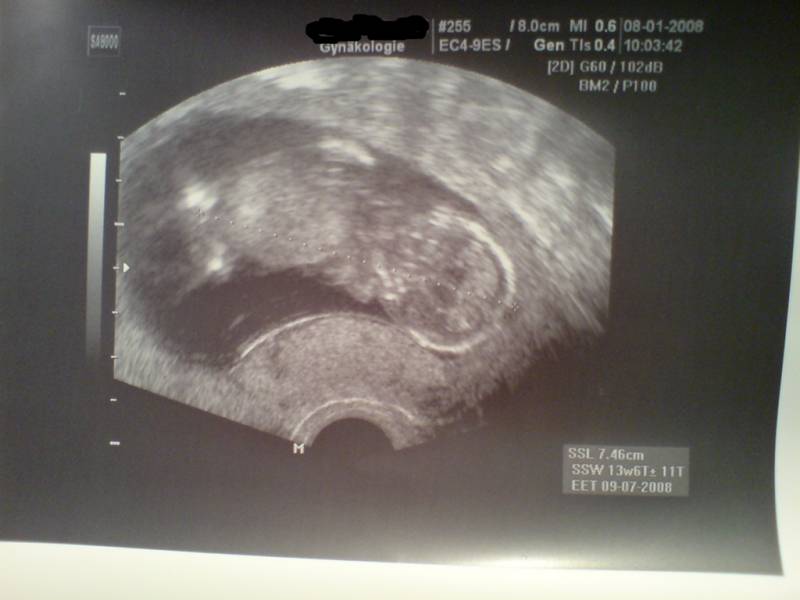

9+5_1 10. SSW Datum 19.05.2008 10. SSW